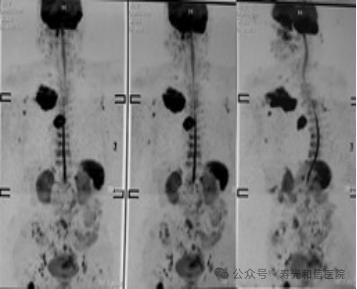

与PET-CT依赖放射性示踪剂、CT存在电离辐射不同,DWIBS完全基于磁场和射频波,无辐射风险,适合儿童、孕妇及需要多次随访的患者。对于有家族肿瘤史、携带致癌基因突变(如BRCA1/2)或长期接触致癌物的人群,DWIBS可作为无创筛查工具,帮助早期发现病变。在已确诊的肿瘤患者中,DWIBS可快速判断是否存在全身转移,指导分期和治疗方案选择。研究显示,其对骨转移的检出率与PET-CT相当。

(躯干类PET观察肿瘤转移情况)